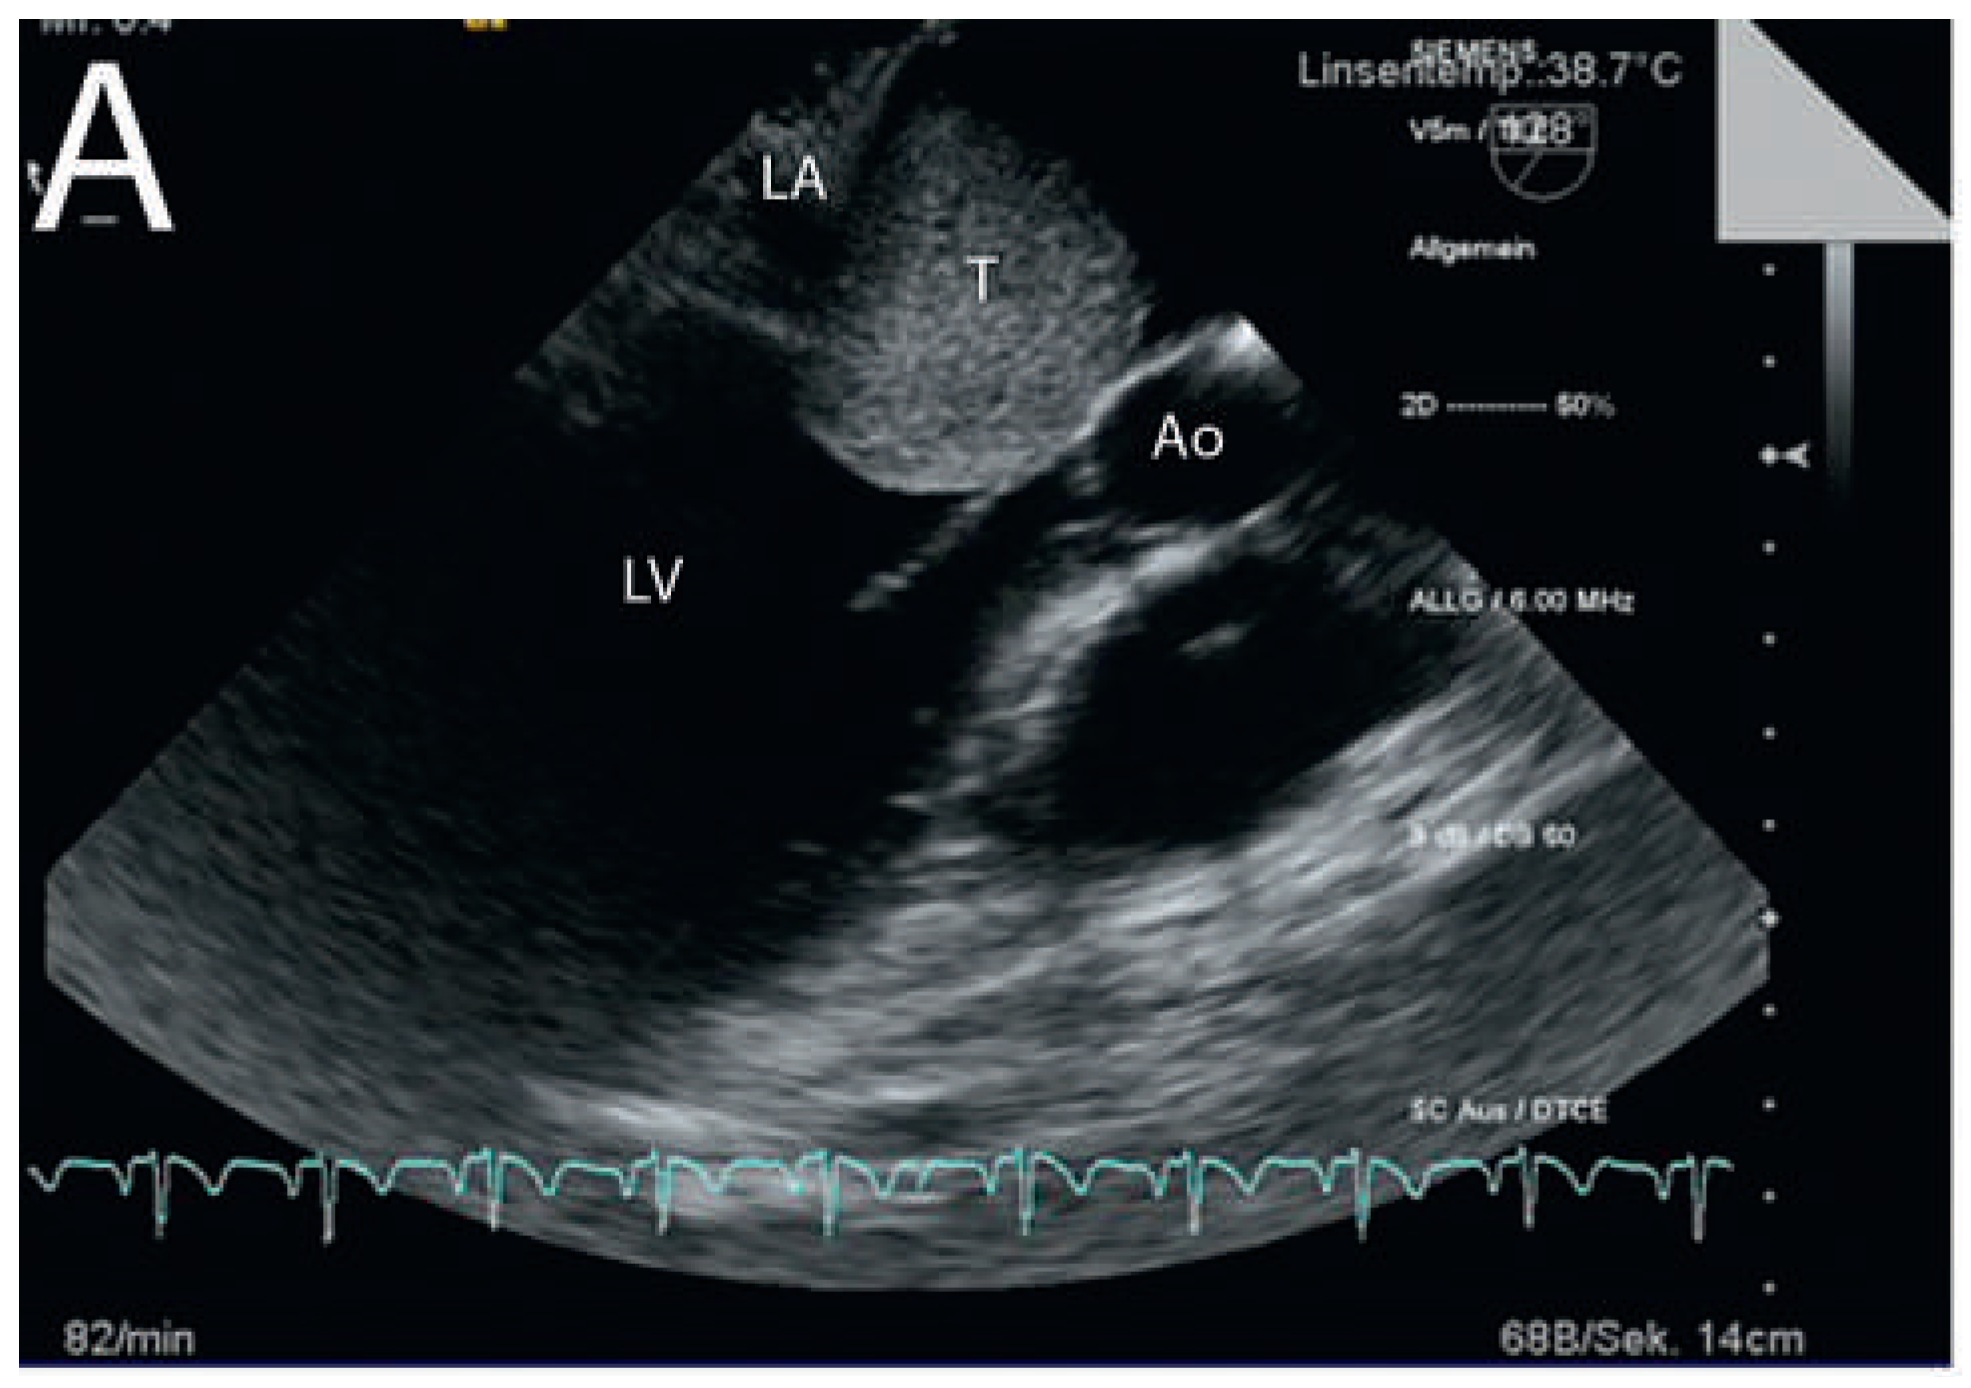

A 59-year-old patient without a history of heart failure complained of progressive dyspnoea of two weeks’ du- ration. The chest radiograph showed a large left-sided pleural effusion, but the symptoms did not improve af- ter drainage of 1700 ml fluid. Transthoracic echocardi- ography demonstrated an unclear left atrial mass. Transoesophageal echocardiography showed an elon- gated, free floating mass originating from the left lower lung vein. This mass reached up to the posterior mitral leaflet and partially obstructed ventricular diastolic filling (Figure 1A). Computer tomography confirmed a cen- trally located mass measuring 7 × 6 × 6 cm and infil- trating the left lower lung vein and left atrium (Figure 1B). After metastatic disease was ruled out via positron emission tomography and brain-magnetic resonance imaging, the patient was scheduled for surgery. In toto resection of the tumour bulk including left pneumec- tomy, partial resection of the left atrium and recon- struction of the atrium with xenopericard was per- formed under extracorporeal circulation (Figure 1C). His- topathological examination of the resected tissue showed a low-differentiated adenocarcinoma (Figure 1D). The patient was discharged 14 days postoperatively. At follow-up after 18 months the patient is free of dysp- noea and well.

Figure 1. (A) The mass reaches up to the posterior mitral leaflet and partially obstructs ventricular diastolic filling. T = tumour; LA = left atrium; LV = left ventricle; Ao = aortic outflow. (B) Computer tomography: a centrally located mass, measuring 7 × 6 × 6 cm, infiltrating the left lower lung vein and left atrium. T = tumour. (C) In toto resection of the tumour bulk including left lung and a part of the left atrium. T = tumour. (D) Histopathological examination of the resected tissue showed a low-differentiated adenocarcinoma. * = remaining lung parenchyma; # = atrial myocardium; arrows indicating tumour infiltrating the endocardium.